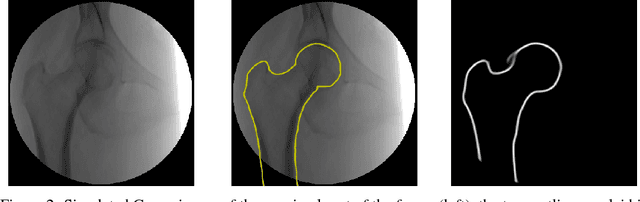

Abstract:We propose approaches based on deep learning to localize objects in images when only a small training dataset is available and the images have low quality. That applies to many problems in medical image processing, and in particular to the analysis of fluoroscopic (low-dose) X-ray images, where the images have low contrast. We solve the problem by incorporating high-level information about the objects, which could be a simple geometrical model, like a circular outline, or a more complex statistical model. A simple geometrical representation can sufficiently describe some objects and only requires minimal labeling. Statistical shape models can be used to represent more complex objects. We propose computationally efficient two-stage approaches, which we call deep morphing, for both representations by fitting the representation to the output of a deep segmentation network.